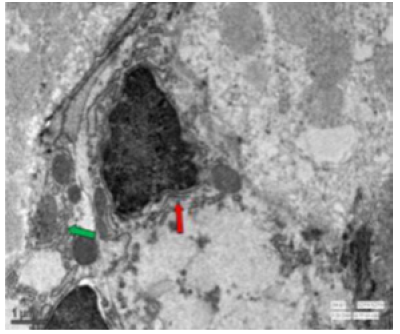

Transmission Electron Microscopic Changes

In the duodenum of the control rat, the enterocytes had a regular microvillus border, tiny finger-like projections and a few granular bodies (Figure 47). In the intranuclear region of the enteroendocrine cells, numerous tiny, electron-rich spheroidal granules were present (Figure 48). The microvilli were reduced in height and were damaged (Figure 49). The fluoridated duodenal mucosa had fat droplets suggesting lipid accumulation, vacuolations, a thickened epithelial membrane, multivesicular structures exhibiting endocytic activity and discernible widening of spaces (Figure 50). There were aberrant absorptive cells, granular bodies along mitochondria (Figure 51). The endoplasmic reticulum exhibited vacuolization. Goblet cells were seen among the cellular protrusions (Figure 52). The duodenal mucosa in fluoridated rats appeared flat with the absence of villi, indicating significant damage to the intestinal structure essential for nutrient absorption (Figure 53). Irregular nuclei along with some vacuolation were evident in fluorotic rats. (Figure 54). The jejunum in the control rat revealed normal mitochondria distinctly characterized by its outer membrane and well-developed cristae (Figure 55). Oval basal nuclei surrounded by nuclear membrane were visible in the cells. Several secretory granules and vesicles were present in the cytoplasm (Figure 56). Small intestinal crypts of Lieberkühn included Paneth cells, specialized epithelial cells. The nuclear membrane enclosing the basal nucleus were also seen (Figure 57).

In the fluoride-treated rat, the endoplasmic reticulum had dilated cisternae, contained the virus particles, characterized by an electron-dense core enveloped by one or two membranes (Figure 58). Under the microvilli, a noticeable terminal web was seen and prominent lateral interdigitations were visible between the cells, suggesting complex folding or invaginations of cell membranes. Additionally, the mitochondria appeared swollen with few disintegrated cisternae (Figure 59). The jejunum of fluorotic rats displayed vacuolations. The presence of lysosomes and vesiculated RER was observed in the cytoplasm (Figure 60).

Figure 58: Transmission electron micrograph of jejunum of rat treated with 600 mg fluoride for 40 days showed virus particles (↑) having electron dense core surrounded by one or two membranes. X 5000.

Figure 59: Transmission electron micrograph of jejunum of rat treated with 600 mg fluoride showing interdigitations (↑) swollen mitochondria with few disintegrated cristae. Dilated reR (↑) was also seen. X 2550.

In the ileum of control rat, distinct defensin-rich granules were visible within the Paneth cells, indicating their role in innate immune defence. Furthermore, mitochondria and different secretory granules were also present (Figure 61) and had rough endoplasmic reticulum throughout the cytoplasm (Figure 62). In fluoridated rats, the Golgi apparatus of the ileal tissue appeared aberrant and hypertrophied. The mitochondria had lost their characteristic appearance and were obscured suggesting that high fluoride exposure disrupts cellular structures and functions within the ileum (Figure 63). Significant vacuolations, suggestive of the presence of spaces within the tissue, disintegrated mitochondria and irregularly shaped nuclei were visible (Figure 64). The ileum exhibited irregularities in the rough endoplasmic reticulum (rER) and disruptions in other cytoskeletal components (Figure 65).

Figure 60: Transmission electron micrograph of jejunum of rat treated with 600 mg sodium fluoride showing vacoulations (↑), vesiculated reR (↑) and some lysosomes. X 2550.

Figure 62: Transmission electron micrograph of ileum of rat treated with 600 mg fluoride showing abnormal mitochondria (↑) and abnormal golgi apparatus (↑). X 9900.

Figure 63: Transmission electron micrograph of ileum of rat treated with 600 mg fluoride showing vacoulations (↑), disintegrated mitochondria. X 7000.

TEM studies have revealed significant ultrastructural alterations in the small intestine of rats exposed to sodium fluoride. Degeneration of cell organelles, including the endoplasmic reticulum, Golgi body, mitochondria, nucleus, mucous membrane, and villi, and severe damage to the irregularly shaped fenestrated cell organelles were among the morphological consequences of the fluoride administration, as revealed by the ultrastructural analysis. TEM images showed swelling of mitochondria, a disruption of the endoplasmic reticulum, and an increase in electron-dense granules within these cells. These changes suggested that fluoride interferes with cellular metabolism and protein synthesis. The present study demonstrated mitochondrial injury and rough endoplasmic reticulum proliferation in fluoride-treated rats [23,24]. In the tissues, black particles emerged. Several ancillary approaches involving light microscopy [25] and these black granules were lipid droplets [26]. In present study, the mucosa appeared flat, and the villi were practically non-existent. Loss of brush border, irregular nuclei and vacuolation of some enterocytes were observed using transmission electron microscopy. The villi exhibited shortening, blunting and distortion [27]. Intestinal defensin expression in Paneth cells was employed as a developmental marker for Paneth cell maturation [28].